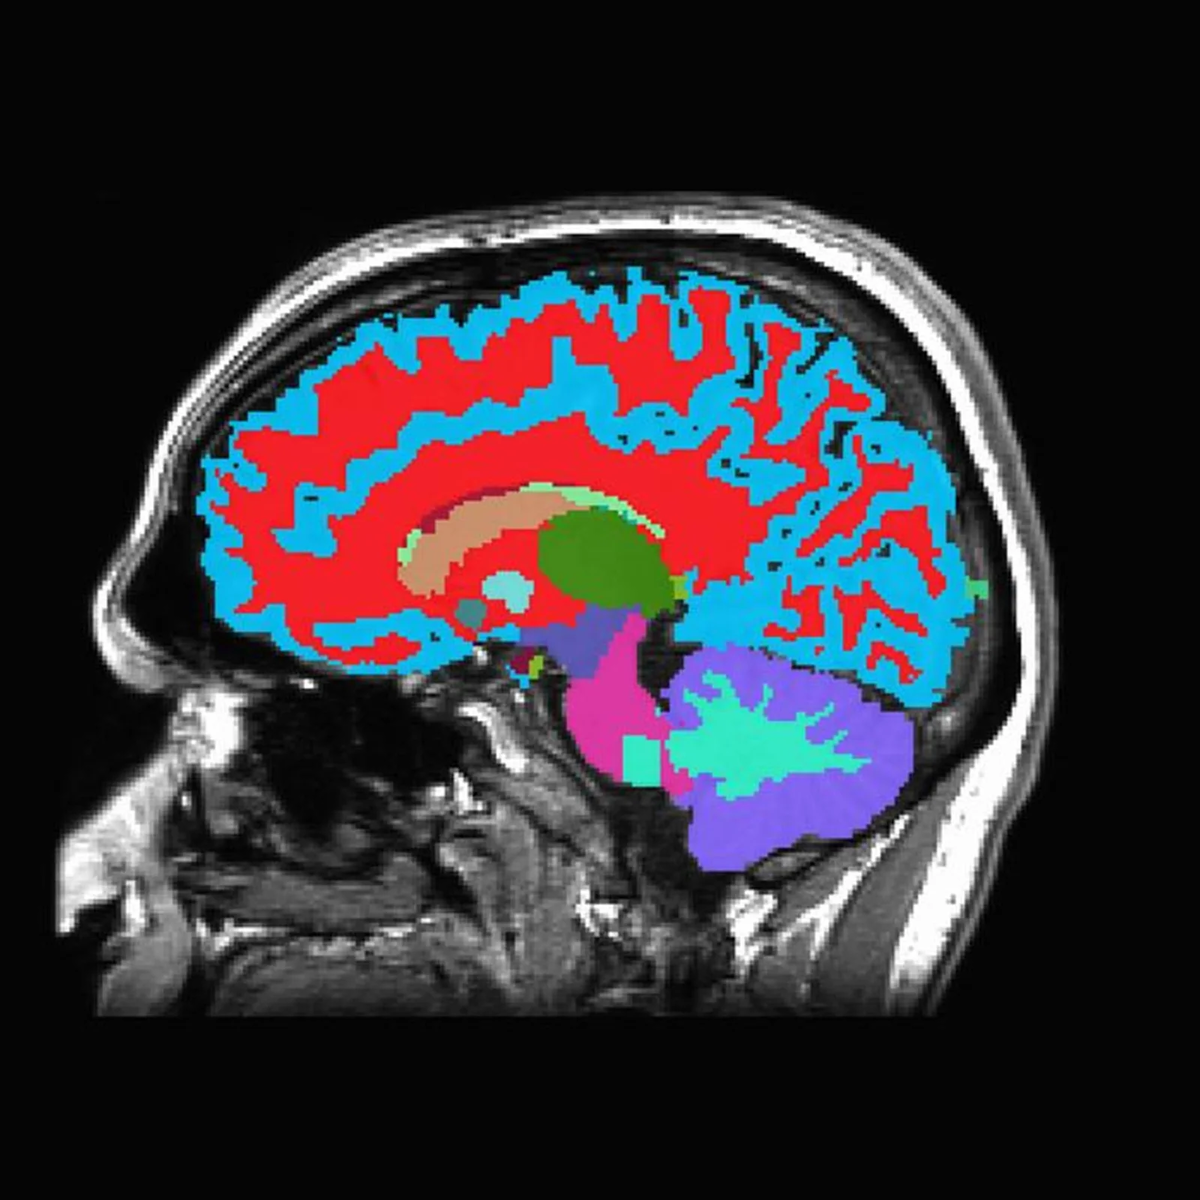

• Активность мозга регистрировалась с помощью высокоплотной электроэнцефалографии.

Что происходит в мозге?

Во время эпизодов «пустоты ума»:

1. Снижается связность между отдалёнными нейронными сетями.

2. Нарушается обработка зрительной информации, особенно её поздняя стадия, связанная с осознанным восприятием.

3. Замедляются реакции и растёт число ошибок в задачах.

Учёные предполагают, что это напоминает кратковременный «сон наяву», когда отдельные участки мозга временно переходят в режим, близкий ко сну.